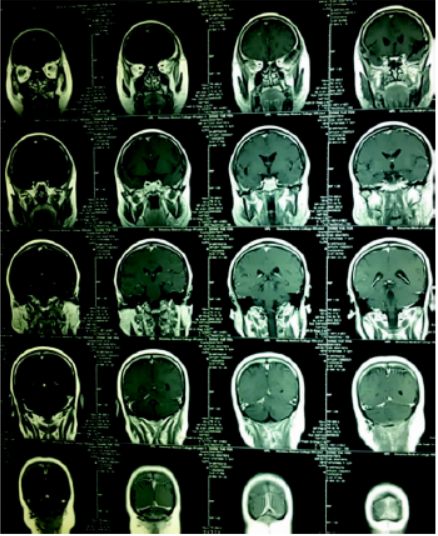

术后随访:术后3个月随访,该患者因存在精神分裂症,放化疗科医生不建议行放化疗,嘱定期复查,复查结果如图6、7。

图6 术后三个月复查

图7 术后三个月复查